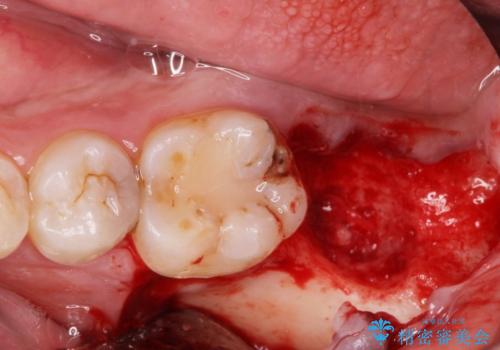

まず徹底的に虫歯を取り除き、保存が出来ない部位は抜歯(親知らずを含む)を行い、根管治療が必要な部位は精密根管治療を行いました。

また、虫歯が歯肉の中まである場合はAPF(歯肉弁根尖側移動術)も行なっています。